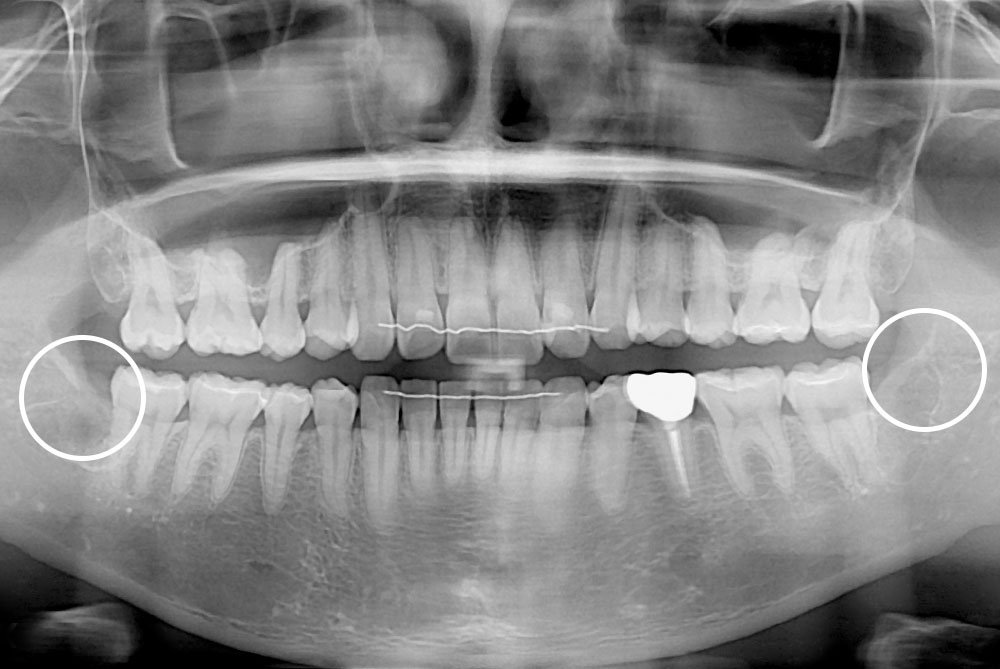

[사랑니] 매복 사랑니 발치

치료후 : 2022-02-28

세종치과는 구강악안면외과학 박사이신 원장님이 발치하는 치과입니다.